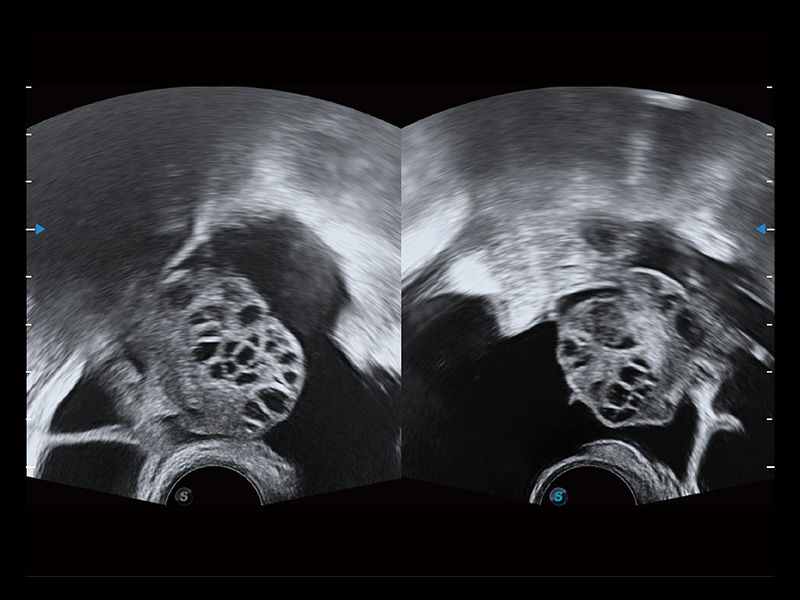

“生育问题”即关系民族复兴,也关系亿万家庭的幸福。随着婚育年龄推迟、社会压力增加等因素,越来越多人群也面临着“生不出、生不好”的问题。辅助生殖作为治疗不孕不育最有效的方法之一,也逐渐成为育儿新希望。而超声检查能为生殖需求人群的初诊评估提供宝贵的信息。 P20 Elite是百老汇电子游戏官网匠心打造的一款生殖应用型彩超。她继承百老汇电子游戏官网高端极光平台,突破性地将多款新型芯片及硬件模块进行整合,均衡了高端系统性能与小巧灵动机身。P20 Elite卓越的图像质量搭载专科探头,旨在为您提供全面的辅助生殖解决方案。

P20 Elite配备了丰富的生殖探头群和临床应用功能,在卵泡监测、穿刺取卵、胚胎移植、妊娠确认等领域,为生殖需求人群提供了新的临床机会,重新定义高端超声如何应用于生殖健康检查。